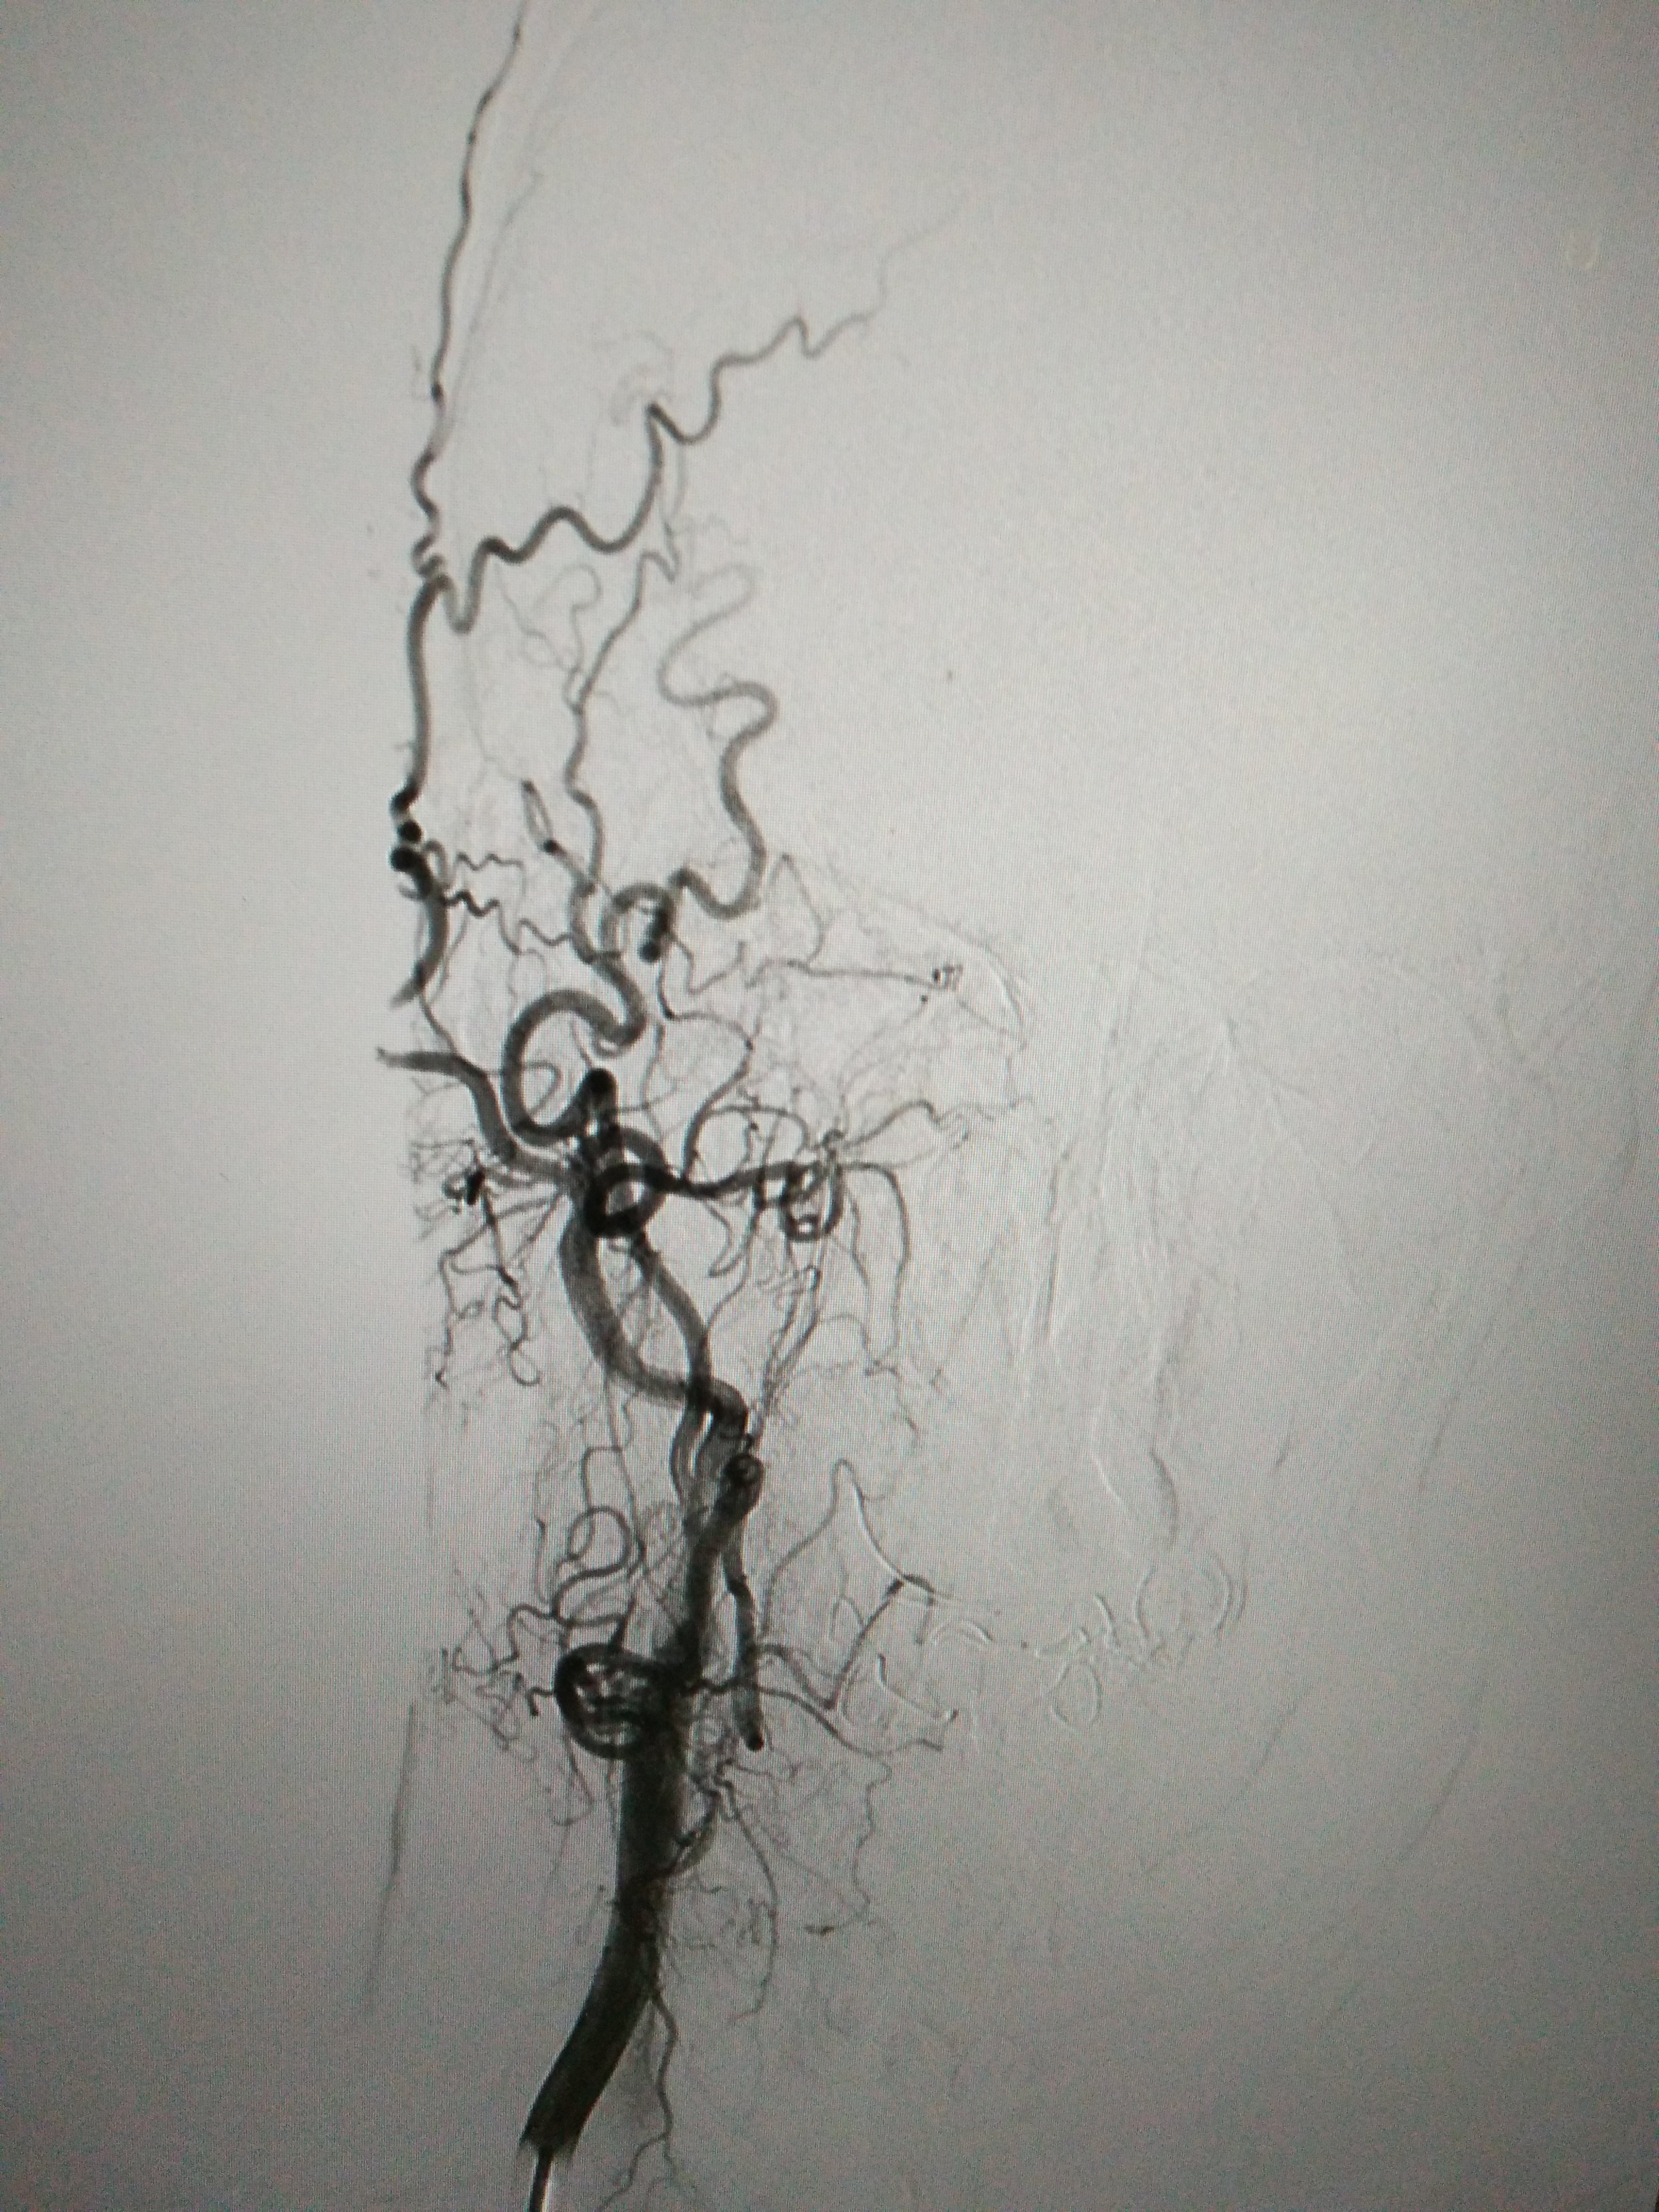

全脑血管造影显示:右侧大脑中动脉闭塞

右侧颈内动脉全程闭塞(正位)

路图下显示右侧颈内动脉闭塞.

右侧颈内动脉慢性闭塞 右侧大脑中动脉闭塞,机械取栓 颈动脉支架置入

右侧大脑中闭塞,左侧颈内动脉闭塞.